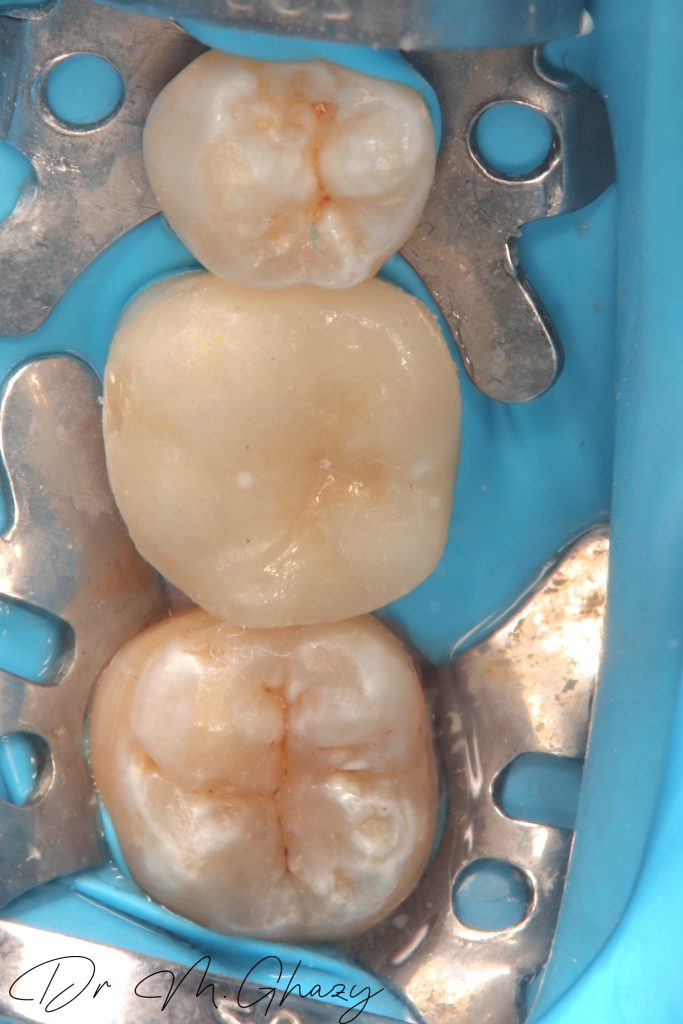

Occlusal reduction and cavity optimization done

Isolation

Selective acid etching

Surface treatment for lithium dislicate by 9.5% HF acid